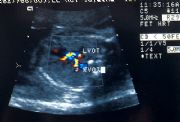

Color flow Doppler of fetal

heart to show cross over of

Left Ventricular Outflow Tract

(LVOT) and Right Ventricular

Outflow Tract (RVOT)